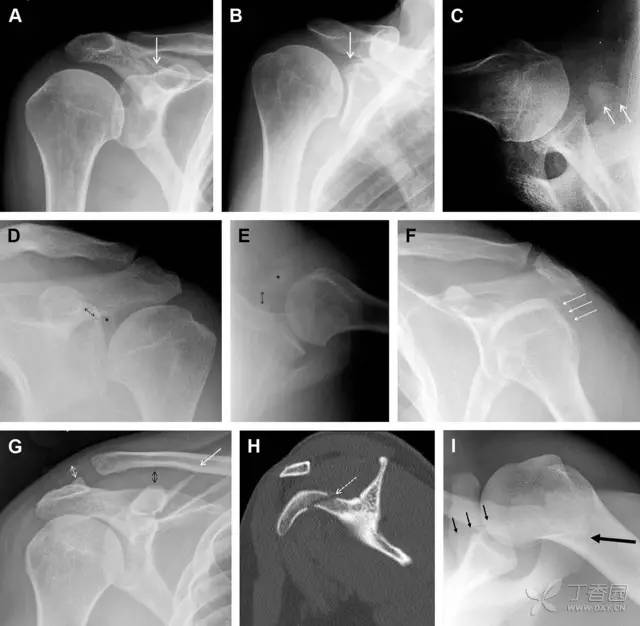

26 喙突骨折

喙突骨折可发生于直接*力暴**、肩关节脱位过程的肱骨头撞击、以及撕脱骨折(肱二头肌短头、喙肱肌)。

其中喙突基底部骨折最多见,常发生于直接*力暴**或肱骨头前脱位,骨折可延伸至关节盂。

而撕脱骨折多为喙突尖部的骨折。需要加拍腋位和 Stryker 位片(X 射线束以喙突为中心并头倾 10°,手臂外展,这样可以避开骨性结构的阻挡)。

有时,负重位片可发现并存的肩锁关节脱位,将有助于诊断。

图 4 喙突骨折。66 岁男性患者,猎枪射击后右肩前方疼痛。(A)内旋位前后位片投影隐约可见喙突基底部骨折(白色箭头),(B)外旋位前后位片投影结构存在重叠,(C)腋位投影时可良好显示。(D~F)喙突骨折伴 Hill-Sachs 损伤:肩关节脱位后慢性疼痛,喙突骨折块(*)向前外侧移位(双箭头),在外旋前后位(D)及腋位(E)片上均可显示,在内旋位前后位(F)片上,喙突被遮挡,但可见肱骨头 Hill-Sachs 损伤。(G、H)喙突骨折伴肩锁关节脱位,肩锁关节分离(白色双箭头),而喙锁间距正常(黑色的双箭头),应警惕喙突骨折。(I)喙突与肩峰骨化中心:对于未成年人,喙突与肩峰骨化中心可同时存在,易与骨折混淆,此时,拍对侧的 X 线片对比将有助于诊断。

27 肩峰骨折

肩峰骨折为高能量损伤,多由直接*力暴**导致,好发于中青年患者,多伴有肩关节其它结构损伤。有必要拍摄 Rockwood 位(前后位片,X 线束尾倾),特别有利于显示肩峰下部及肩峰下间隙。

图 5 肩峰骨折。内旋位前后位(A)片上,骨折线几乎被喙突完全遮挡, 但是在标准前后位(B)和腋位(C)片上可见骨折线

28 骨折伴盂肱关节不稳

肩关节是最容易脱位的关节之一,肩关节脱位常伴随其它结构的损伤,如血管神经损伤、肩袖损伤、盂唇损伤、Bankart 损伤等。脱位本身诊断往往是明确的,容易被轻忽的是其继发的伴随损伤。

需要仔细评估肱骨头、大结节、关节盂边缘、肩峰、喙突等结构。典型的 X 线投射角度包括:内旋位前后位片、外旋位前后位片(Grashey 位)、侧位(肩胛骨 Y 位)、腋位片以及改良腋位片。

图 6 肩关节前脱位伴有 Hill–Sachs 和 Bankart 损伤:(A~C)肱骨头后外侧撞击骨折,白色箭头所示为骨折的内侧边界;(A)内旋位前后位片,(B)「V」形压缩骨折的下边界(虚线短箭头),(C)Garth 位(轴向投影)示 Hill–Sachs 损伤(虚线和实线折箭头),特别是对骨性 Bankart 损伤的诊断有帮助。(D、E)MRI 进一步证实了损伤

图 7 肩关节后脱位伴有反 Hill–Sachs 损伤。(A)外旋位前后位片可见一硬化带(黑箭头),此「凹槽征」与肱骨头关节面平行;(B)腋位片进一步证实了骨折的存在